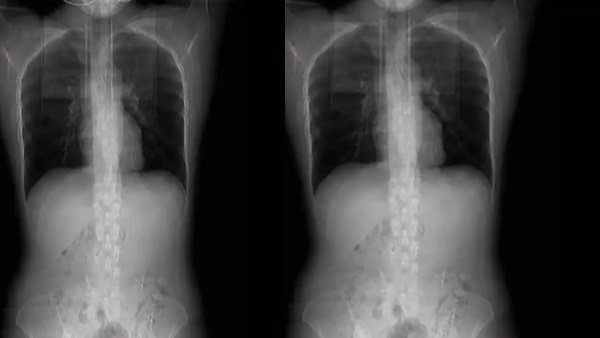

आमतौर पर लोग चटपटा मसालेदार खाना पसंद करते हैं, अगर आप भी उन्हीं मसालेदार खाना खाने के शौकीन में से एक हैं तो आपको सतर्क हो जाने की जरूरत है क्योंकि एक महिला की मसालादार खाने से उसकी चार पसलियां टूट गई। ये मजाक नहीं सच है। चार पसलियां टूटने के बाद उठने बैठने को मजबूर हो चुकी महिला इन दिनों सुर्खियों में हैं उसके सीने का एक्सरे सामने आया है। जिसमें उसकी तीन पसलियां टूटी नजर आ रही हैं।

महिला का डॉक्टरों ने जब सीटी स्कैन किया गया तो पता चला कि हुआंग की चार पसलियां टूट गई हैं। डॉक्टरों ने उसकी छाती पर पट्टी बांध दी और उसकी पसलियों को ठीक करने के लिए पूरा एक महीने तक बेड रेस्ट करने की सलाह दी है।